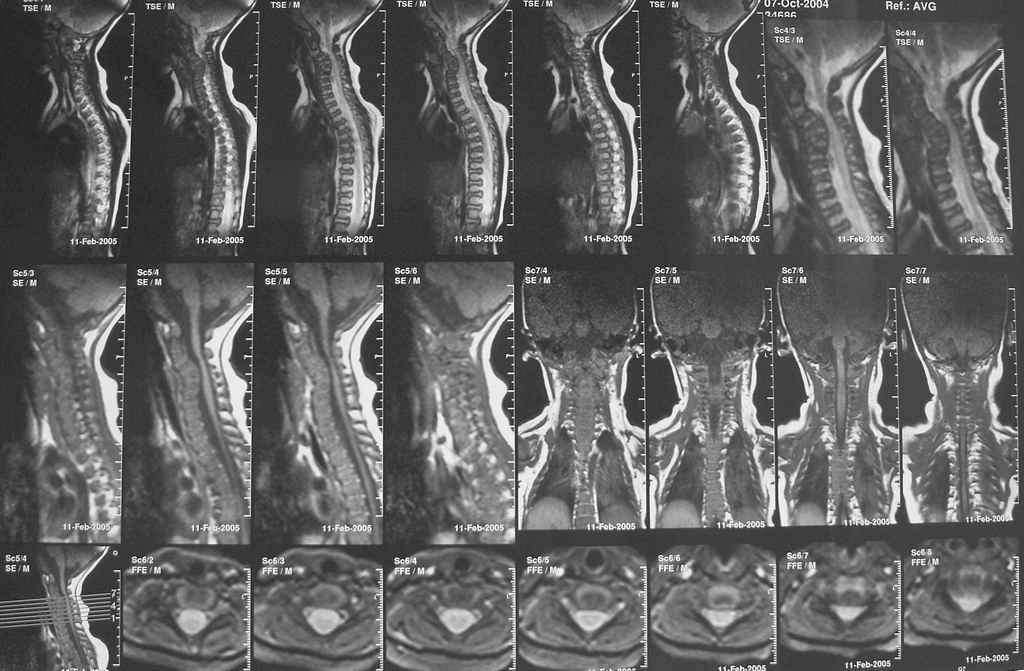

Девочка 5 месяцев, дочь коллеги, врача-анестезиолога, тетрапарез, в ногах спастический в руках - вялый, усугубившийся после "мануальной терапии".

Данные рентгена,КТ и МРТ прилагаются. Кроме того, имеется двухсторонний врожденный вывих бедра.По совокупности данных - болезнь Ларсена.В шейном отделе - дисплазия и гипоплазия суставных отростков С3-С5 с передним подвывихом и антелистезом, патологическим кифозом и стенозом позвоночного канала до 55% от исходного (5 мм при исходном 9 мм). Spina bifida occulta в 5 сегментах, в том числе расщепление задней дуги атланта, агенезия его передней дуги. Признаки спинальной компрессии и диффузной миелопатии на уровне стеноза.Вопрос - возможно ли в таком нежном возрасте оперативное лечение и вообще, какая должна быть тактика ?